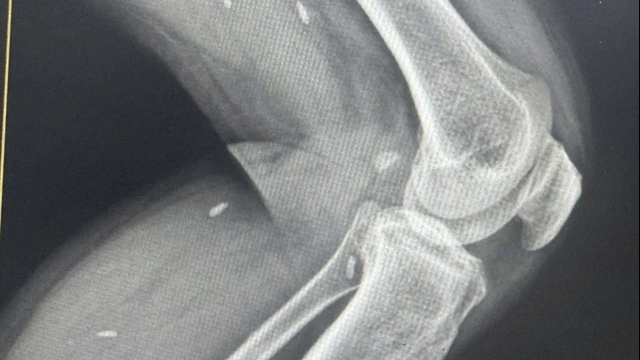

| Hình ảnh trước và sau can thiệp cho bệnh nhân |

Ê kíp can thiệp mạch quyết định can thiệp cầm máu bằng phương pháp chụp và nút mạch các khối u số hóa xóa nền (DSA). Kết quả ghi nhận nhiều nhánh tân sinh mạch vùng hầu, họng, lưỡi được cấp máu từ nhánh của động mạch cảnh ngoài hai bên; Chọn lọc vị trí có tân sinh mạch tiến hành bơm tắc bằng hạt nhựa (PVA-polyvinyl alcohol), kiểm tra thấy tắc hoàn toàn sau 80 phút can thiệp; Tình trạng huyết động ổn. Hiện tại bệnh tỉnh, không chảy máu tái phát, dự kiến ra viện trong ngày 11/1/2023.